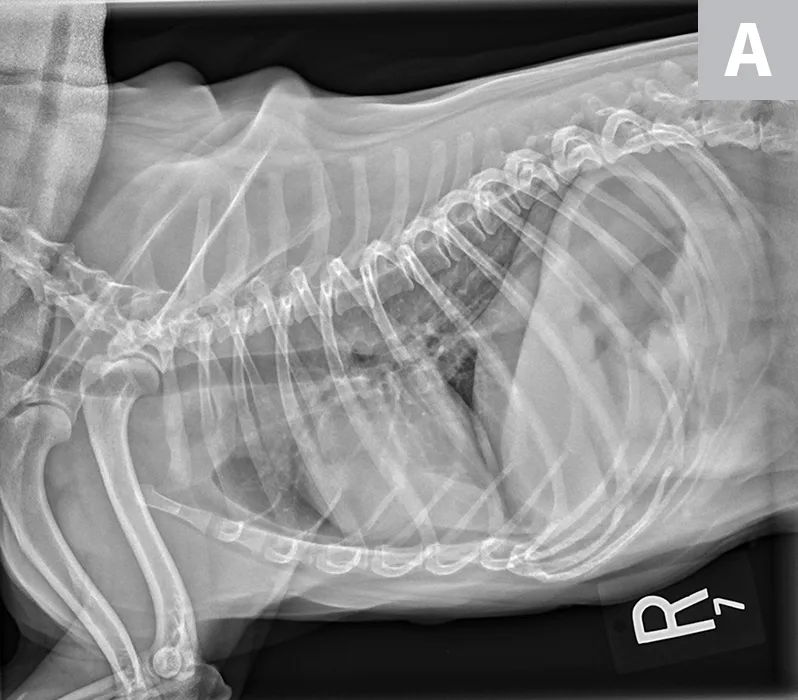

FIGURE 1A

Lateral radiographs of a 2-year-old cat (A) and a 9-year-old cat with increased sternal contact of the cardiac silhouette (B).